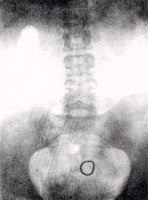

Zleva:

Nahoře:

Pomůcka k

zavádění

Gräfenbergova

kroužku, tři

vzorky

kroužku,

rentgenové

zobrazení

kroužku v

děloze